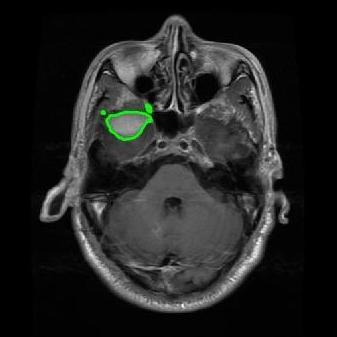

From the above discussions, we have discovered the significant potential of applying Retinex theory to image segmentation and explored its fundamental differences from traditional models. Traditional image segmentation models typically focus on the impact of intensity information on the segmentation results. Therefore, when faced with complex segmentation scenarios, the segmentation results are often affected by lighting, artifacts, and unclear boundaries in the image. As shown in Fig. 1, we present the results of the classical local model LIF [ZHANG20101199] for segmenting brain tumor images along with surrounding tissue edema. The irregular ring-like enhancement caused by the edematous tissue leads to irregular boundaries and low contrast in the images. Consequently, the LIF model can only identify the central necrotic and liquefied regions of the tumor, failing to detect the boundaries and becoming trapped in local minima. In this paper, we draw inspiration from the Retinex theory, which is widely applied in the field of image enhancement. According to Retinex theory, the reflectance component characterizes the intrinsic structural properties of the observed image and preserves texture information independent of illumination variations. By integrating this reflectance component into the level set framework, our model achieves robust segmentation of medical images even under severe intensity inhomogeneity. In addition, a linearized Structural-Prior is proposed to restore intensity consistency and capture local geometric features, thereby improving boundary localization in complex or blurred regions. Furthermore, a relaxed binary level set representation is employed to enhance robustness against noise and to enable accurate tracking of complex contours. Based on these innovations, we propose a novel variational reflectance-based level set model (RefLSM) that simultaneously corrects bias fields and performs segmentation. Experimental results demonstrate that RefLSM significantly outperforms conventional level set methods in both segmentation accuracy and robustness. We present the results of our model segmenting the two brain tumor images mentioned above in Fig. 2.

To address the challenge of segmenting images with severe intensity inhomogeneity, we propose a linearized structural prior that directly operates on the reflectance component . Reflectance-based structural information is more robust to illumination variations and bias field distortions, helping preserve weak edges and subtle anatomical boundaries. As shown in Fig. 2, our method can accurately delineate tumor boundaries and surrounding edema even under severe inhomogeneity, where traditional intensity-based models often fail. The proposed prior aligns smoothed reflectance gradients with data-driven directions, enhancing inter-region contrast, preserving weak edges, and stabilizing the evolution of . Formally, we define the linear structure operator as the gradient field of the smoothed reflectance: